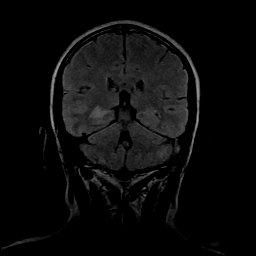

女性,47岁。mri号03027,外伤致头痛9天,抽搐一天,原无类似病史。

颞叶前部萎缩,海马萎缩,t2wi海马高信号,支持海马硬化。

双侧海马区t1低,t2高信号。为什么都考虑硬化?发病原因?鉴别诊断:炎症,梗塞等能一下子除外吗?